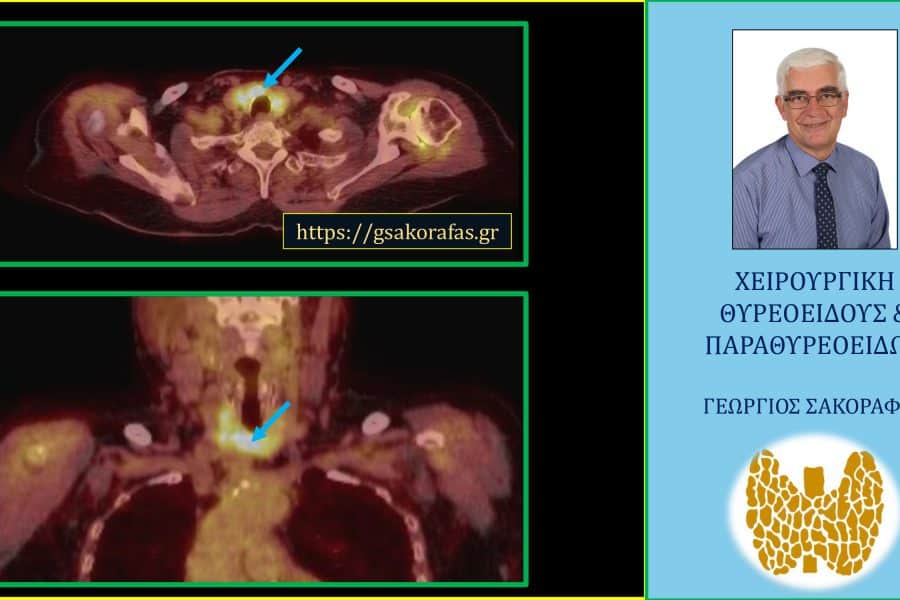

Όζοι θυρεοειδούς και συμπληρωματική θυρεοειδεκτομή (completion thyroidectomy) – με αφορμή ασθενή μας Παρουσίαση ασθενούς Αιτία…